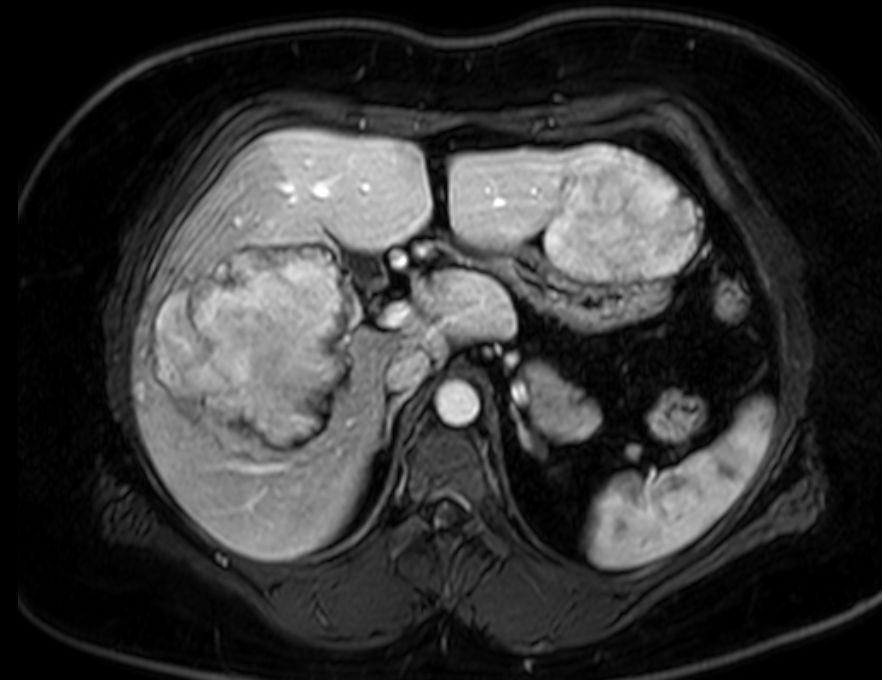

| Fall-Beispiel | 29-jährige übergewichtige Frau, die wegen Diarrhoe zur Aufnahme kam. Bei der Sonographie des Abdomens fiel eine Raumforderung der Leber auf. Das MRT zeigt mehrere Herdbildungen, die gut abgegrenzt sind. | ||